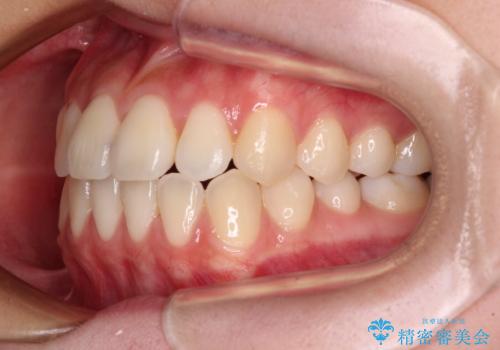

- 前歯のクロスバイトが気になり、インビザラインによる矯正治療を希望して来院された患者様です。

上顎側切歯(上の真ん中から2番目の歯)が舌側転位している場合、インビザラインでは仕上げきれないことが多く、更には無理して動かそうとすると歯髄壊死を起こすリスクが高いと言われています。

インビザラインで歯列を移動する前に、上顎前歯をワイヤー矯正で整え、その後上下歯列をインビザラインにて矯正治療を行うこととしました。

舌側転位している側切歯特有の、切縁の位置が不揃いであったり、根元が内側に引っ込んだ状態であったりという、インビザライン独特の仕上がりになることなく、きれいに整った歯列とすることができました。